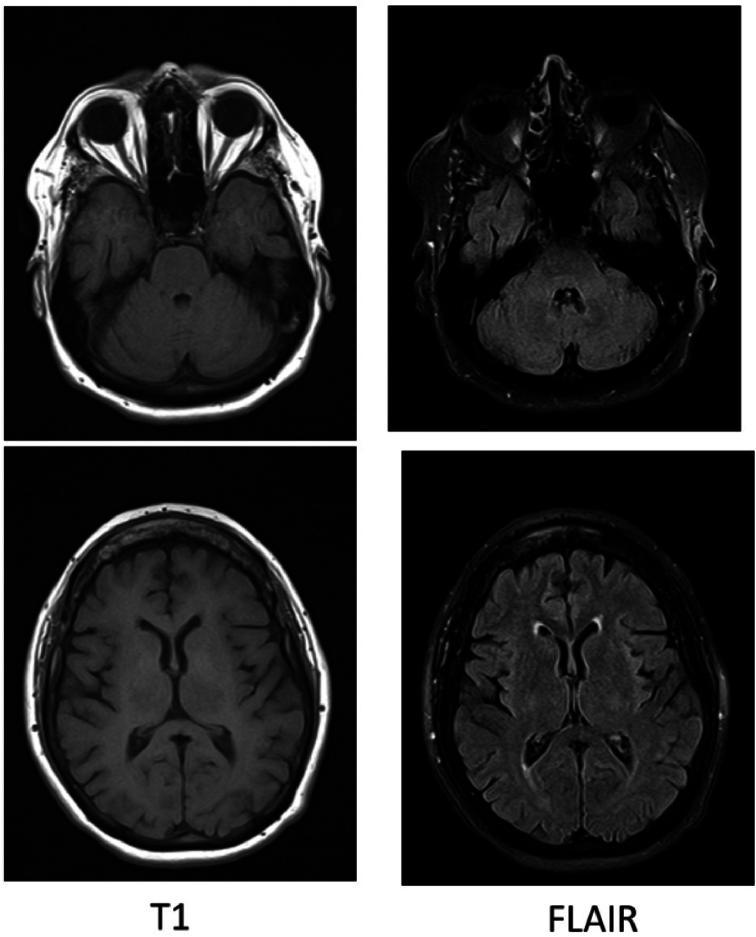

讨论

注射GBCA数小时后,患者出现恶心、呕吐及精神状态改变。患者接受了静脉注射地塞米松治疗,并于第2天出院。两周后的随访中患者无残留缺陷。当前文献表明,应谨慎操作以防止GBCA意外鞘内注射,且剂量>2.0毫摩尔与严重不良反应相关,包括死亡。